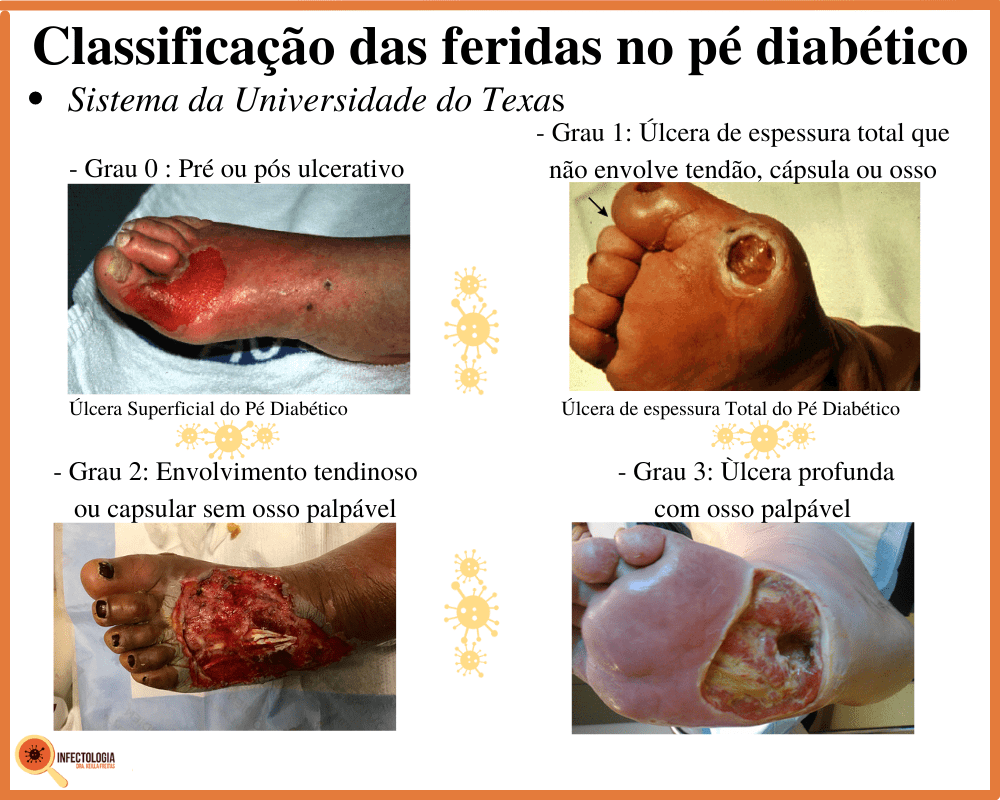

Aqui está o detalhe: infecções em pés diabéticos evoluem rápido.

Podem levar a úlceras profundas e, nos casos mais graves, até à amputação.

Pode confessar: quem nunca testou a água com o pé? Para quem tem sensibilidade térmica reduzida, isso é um erro grave. Queimaduras graves podem ocorrer sem que o paciente sinta desconforto imediato. E o pior: lesões nos pés diabéticos são portas de entrada para infecções, que podem evoluir para úlceras e, em casos extremos, amputação.

Além da temperatura da água, a inspeção diária dos pés é fundamental. Verifique se há cortes, bolhas, vermelhidão ou inchaço. Qualquer feridinha, por menor que seja, precisa de atenção. A prevenção de úlcera diabética é um trabalho contínuo e minucioso.